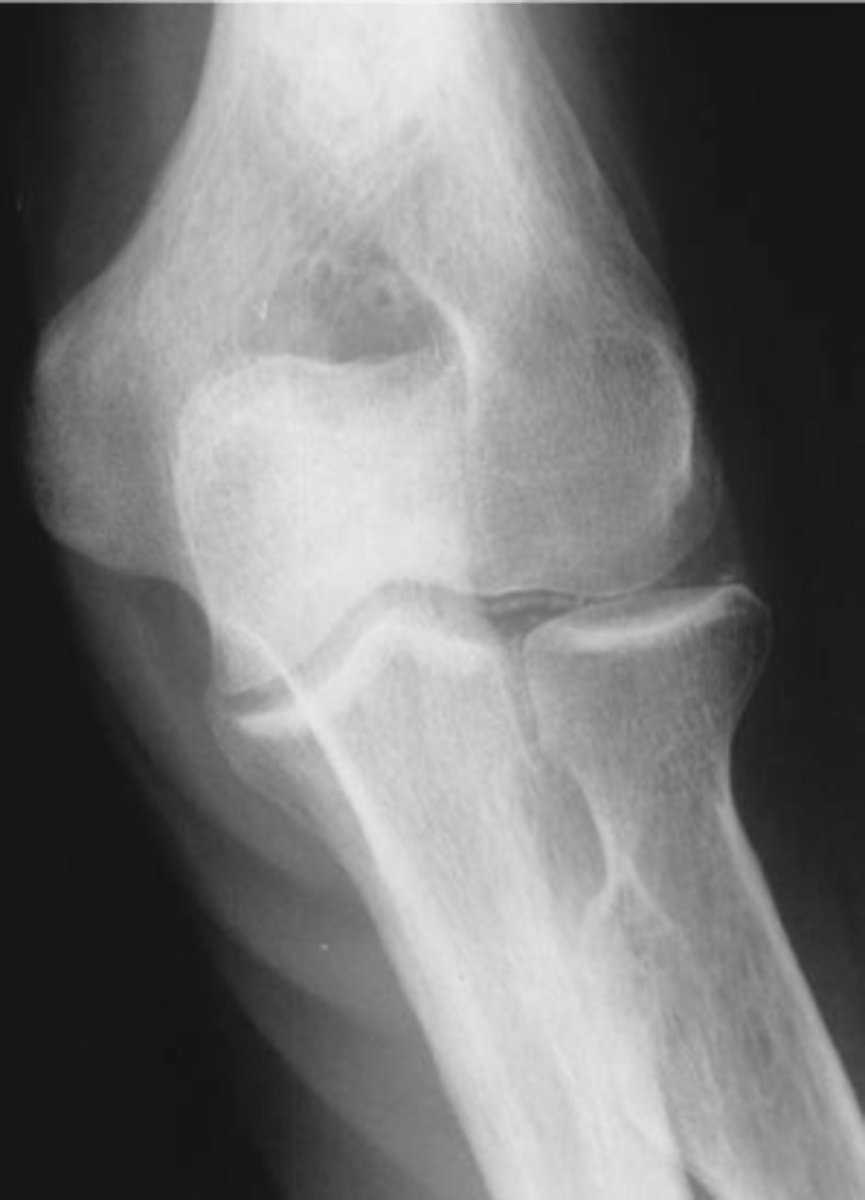

- Soft tissue swelling

- Chondrocalcinosis

- Severe degeneration

- Pyrophosphate arthropathy

- Articular destruction